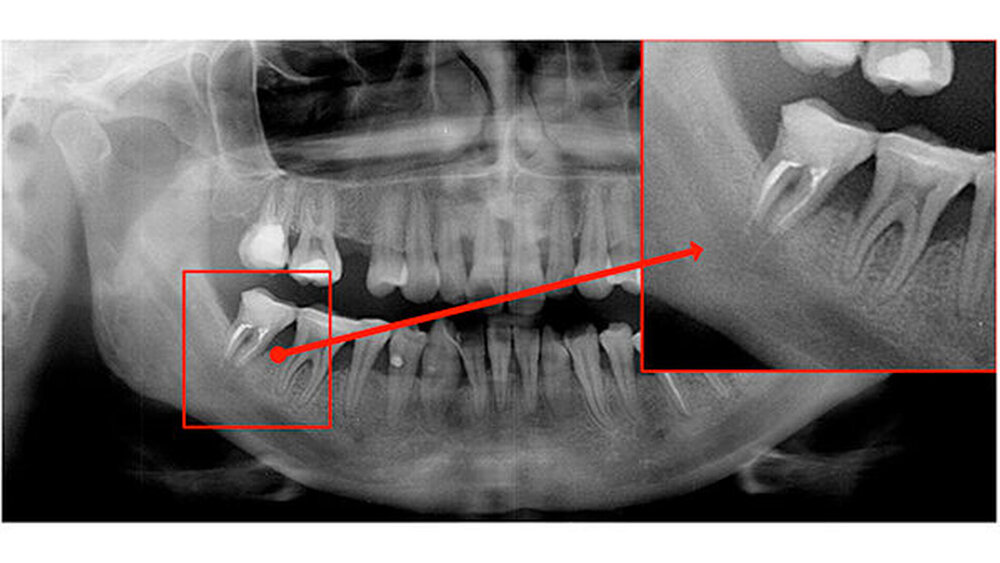

Der Zahn 47 stellte sich parodontal geschädigt und 1-gradig gelockert dar. Das Orthopantomogramm (OPTG) und der anschließend angefertigte Zahnfilm (Abbildungen 2 und 3) zeigten am Zahn 47 apikal weit überextrudiertes Wurzelfüllmaterial. Die Patientin wurde aufgrund der klinischen und der röntgenologischen Befunde sofort an die Klinik und Poliklinik für Mund-, Kiefer- und Gesichtschirurgie überwiesen.